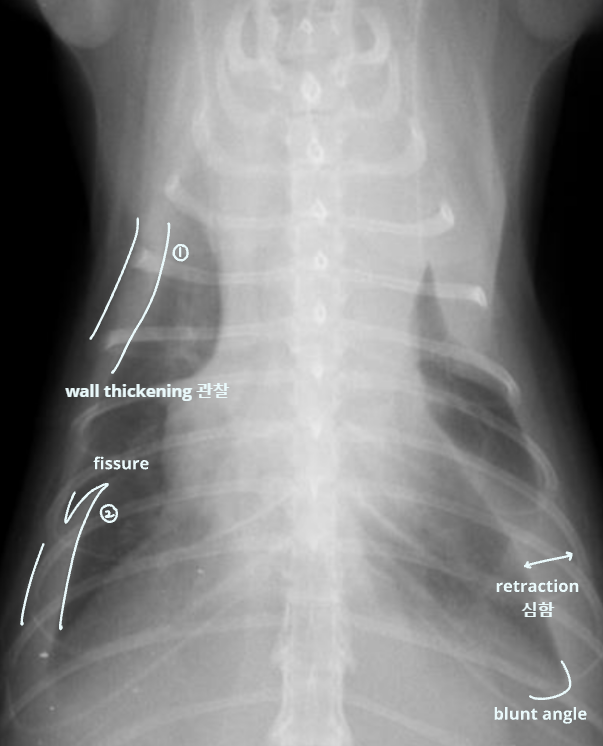

Radiographic signs

interlobar fissure 두껍게 관찰되고,

흉벽이 떨어져 나간 것처럼 보임

- Interlobar fissure widening

- Lung retraction

- Pleural wall thickening

- Scallop sign

- Cardiac effacement

- Blunt angle